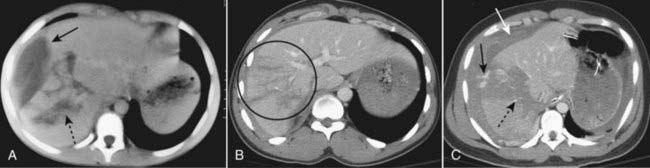

image

Figure 17-7 Hepatic trauma, three different patients.

A, There is a lenticular fluid collection involving the lateral portion of the right lobe of the liver that represents a subcapsular hematoma (solid black arrow). A laceration of the right lobe is also present (dotted black arrow). B, There are multiple lacerations of the right lobe of the liver (black circle). C, Active extravasation of contrast-enhanced blood (solid black arrow) is seen from a large intrahepatic laceration with hematoma (dotted black arrow) and there is both subcapsular blood and hemoperitoneum (solid white arrow).

Figure 17-8 Splenic trauma, three different patients.

A, A crescent-shaped collection of fluid is demonstrated in the subcapsular space which compresses the normal splenic parenchyma representing subcapsular hematoma (solid white arrow). B, This patient has a splenic (solid white arrow) and hepatic (solid black arrow) laceration and a large hepatic contusion (dotted black arrow). There is also pneumoperitoneum (dotted white arrow). C, Active extravasation of contrast-enhanced blood (solid black arrow) is shown along with a large intrasplenic hematoma (solid white arrow).